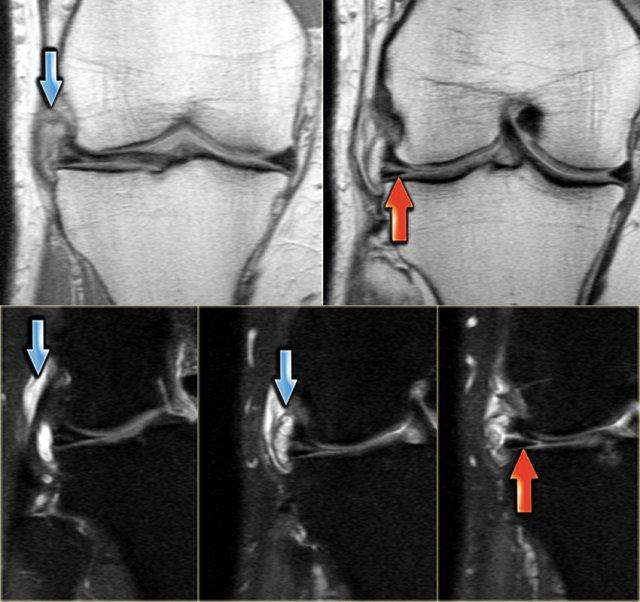

Rách chân sụn chêm

Trước tiên hãy quan sát hình ảnh bên trái và cố gắng nhận diện vị trí rách sụn chêm.

Những tổn thương rách này thường dễ bị bỏ sót.

Ghi nhận một đường rách hướng tâm tại vị trí chân sụn chêm phía sau của sụn chêm trong, đường rách xuyên suốt toàn bộ chiều dày sụn chêm với hình ảnh khe dịch lan dọc theo khuyết tổn thương (mũi tên đỏ).

Rách chân sụn chêm thường đi kèm với hiện tượng thoát vị sụn chêm ra ngoài bờ mâm chày.

Thoát vị sụn chêm trên 3 mm thường liên quan đến các tổn thương rách tại vùng chân sụn chêm (6).

Trong trường hợp bên trái, ghi nhận một đường rách hướng tâm hoàn toàn tách rời sừng sau khỏi chân bám của nó (mũi tên đỏ).

Ngoài ra còn có hình ảnh thoát vị sụn chêm mức độ tối thiểu (hình 1/6).

Đây là một trường hợp rách chân sụn chêm trong khác.

Lưu ý rằng sừng sau không còn bám vào xương chày.

Thay vào đó, có thể thấy một khoảng hở (mũi tên cong).

Những tổn thương rách này rất dễ bị bỏ sót khi người đọc nhầm tưởng sừng sau vẫn bình thường.

Đây là một trường hợp điển hình khác của rách chân sụn chêm trong.

Lưu ý rằng trường hợp này còn kèm theo hình ảnh sụn chêm ngoài dạng đĩa.